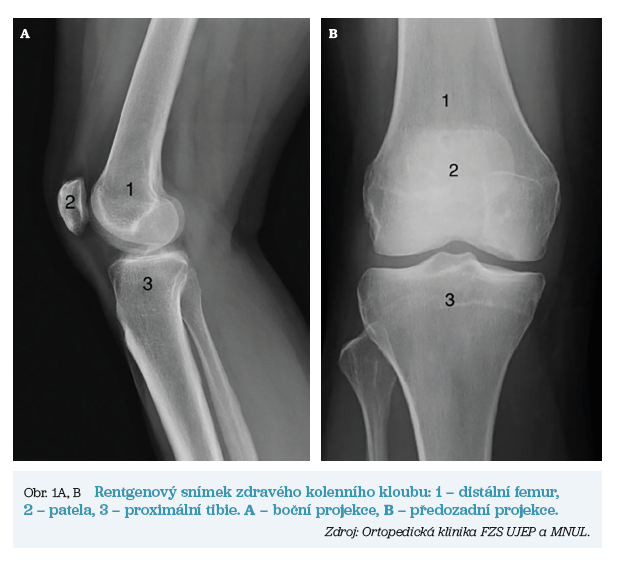

Při implantaci totální endoprotézy (TEP) kolenního kloubu jsou nahrazeny artikulační plochy distálního femuru, proximální tibie a případně i pately.

V obou případech však dochází k postupnému opotřebení kloubní chrupavky, ke zužování kloubní štěrbiny, tvorbě kostních výrůstku (tzv. osteofytů) a v nejzazších fázích až k nekróze kostní tkáně. Pomocí rentgenových snímků lze tyto artrotické změny vizualizovat. Základní anatomii a rozdíly mezi zdravým kloubem a kloubem postiženým artrózou ukazují obrázky 1 a 2.